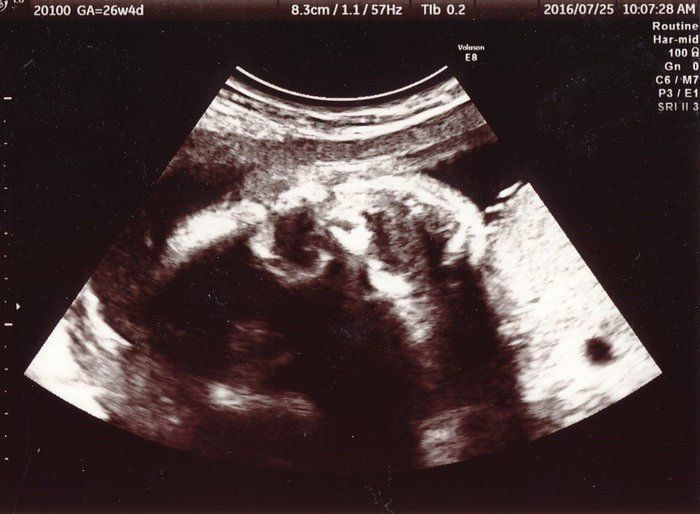

ママにエールさんの妊娠26週目のエコー写真

担当の先生から、赤ちゃんはとても元気で問題ないと言われました。楽しみにしている性別について聞きましたが、先生の返答は「隠していてよく見えない。分かりにくいから、今日のところは女の子かな」と言われました。性別が分かってもいい時期ですが、“逆子”になったり、隠していたり、赤ちゃんはなかなか教えてくれません。でも、無事に生まれてくれれば男女どちらでも嬉しいなという気持ちでした。